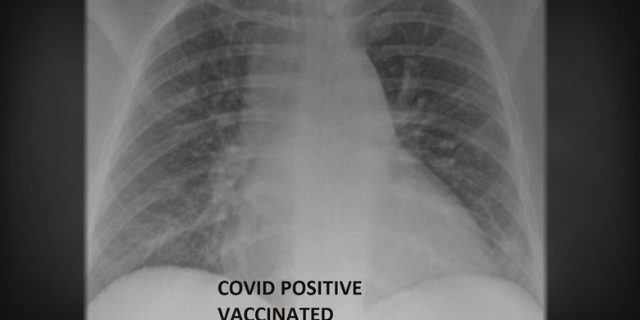

Tak hanya soal gejala saja, namun perbedaan pasien Covid-19 yang sudah divaksin – dan belum dapat dilihat dari kondisi paru-paru. Dikutip dari The Independent, ada dua gambar sinar-C yang disediakan oleh SSM Health. Keduanya, dari pasien yang terinfeksi, namun yang satu sudah vaksin, sementara yang lainnya belum.

Menurut direktur ICU di Rumah Sakit Universitas Louis di Missouri, dr Ghassan Kamel menyebutkan bahwa hasil rontgen paru-paru di atas menunjukkan pentingnya vaksin Covid-19. Warna putih yang terlihat di rontgen menandakan adanya kerusakan yang disebabkan oleh virus.

Kerusakan tersebut bisa jadi bakteri, lendir, maupun sekret. Setidaknya, bagi yang belum divaksinasi membutuhkan oksigen – bahkan, terkadang lebih dari sekedar oksigen. Pasien mungkin membutuhkan ventilator, atau diintubasi dengan ventilasi mekanis dan dibius. Pada dasarnya, mereka mungkin memerlukan alat bantu untuk bertahan.

Sementara itu, hasil rontgen paru-paru pasien yang sudah divaksin menunjukkan kondisi yang cukup baik. Dari gambar di atas, dapat dilihat bahwa organ paru-paru berisi udara – dan ini terlihat dari lebih banyaknya area hitam.